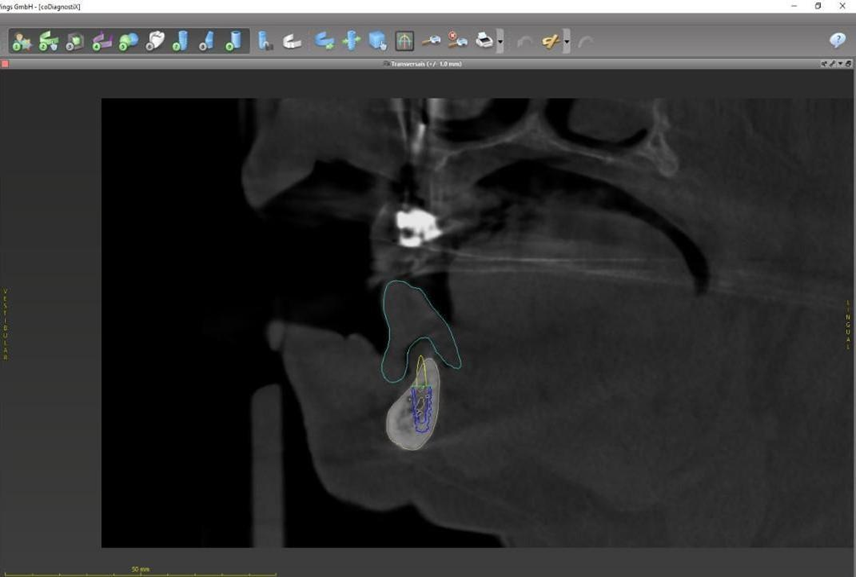

Paciente de 62 anos, do sexo feminino, sem comorbidades e história médica pregressa, apresentava severa reabsorção óssea em regiões anteriores e posteriores da mandíbula devido a uma peri-implantite (Figuras 1A e 1B). Feita a remoção dos implantes, a paciente optou por utilizar uma prótese total mucossuportada até a nova intervenção com prótese do tipo protocolo inferior. Após seis meses, a mandíbula encontrava-se cicatrizada (Figura 2). Como parte do protocolo diagnóstico, foi realizada tomografia computadorizada pela técnica do duplo DICOM. Com a severa perda óssea em região anterior de mandíbula, optamos por realizar a cirurgia de forma guiada, aumentando a previsibilidade e precisão da cirurgia. Os arquivos obtidos foram exportados para o software CoDiagnostiX, possibilitando a realização do planejamento reverso e o subsequente posicionamento virtual dos implantes (Figura 3). Com base no planejamento, optou-se pela instalação de quatro implantes Implacil Osstem CM AR Due Cone (3,5 x 7 mm), associados a mini-cônicos de 1,5 mm (Figuras 4A, 4B, 4C, 4D e 4E). A partir da tomografia da prótese da própria paciente, confeccionaram-se duas guias cirúrgicas: uma guia de pino de fixação (Figura 5) e uma guia de fresagem para a instalação dos implantes (Figura 6). Durante o procedimento cirúrgico, inicialmente foi posicionada a guia de pino de fixação para fresagem dos pinos de fixação e orientação da sequência cirúrgica (Figura 7). Após essa etapa, a guia foi substituída pela guia de fresagem dos implantes (Figura 8), utilizada para a fresagem e inserção dos implantes planejados (Figura 9). Concluída a instalação, optou-se por seguir o fluxo analógico, com a adaptação dos mini-cônicos 1.5 mm (Figura 10), realização da transferência de moldagem com silicona de adição leve e sutura com fio absorvível Vycril 6-0. O guia inicial foi adaptado com broca Maxicut, possibilitando sua utilização como molde de orientação para o laboratório protético (Figura 11). Após a moldagem, foram posicionadas as tampas de proteção sobre os implantes. Na fase protética, transcorridas 48 horas do procedimento cirúrgico, foi realizada a prova clínica da barra metálica e dos dentes (Figura 12). Na etapa subsequente, 72 horas após a cirurgia, procedeu-se à instalação e entrega do protocolo mandibular inferior e radiografia prévia, reabilitando funcional e esteticamente a paciente em curto espaço de tempo (Figuras 13A e 13B).